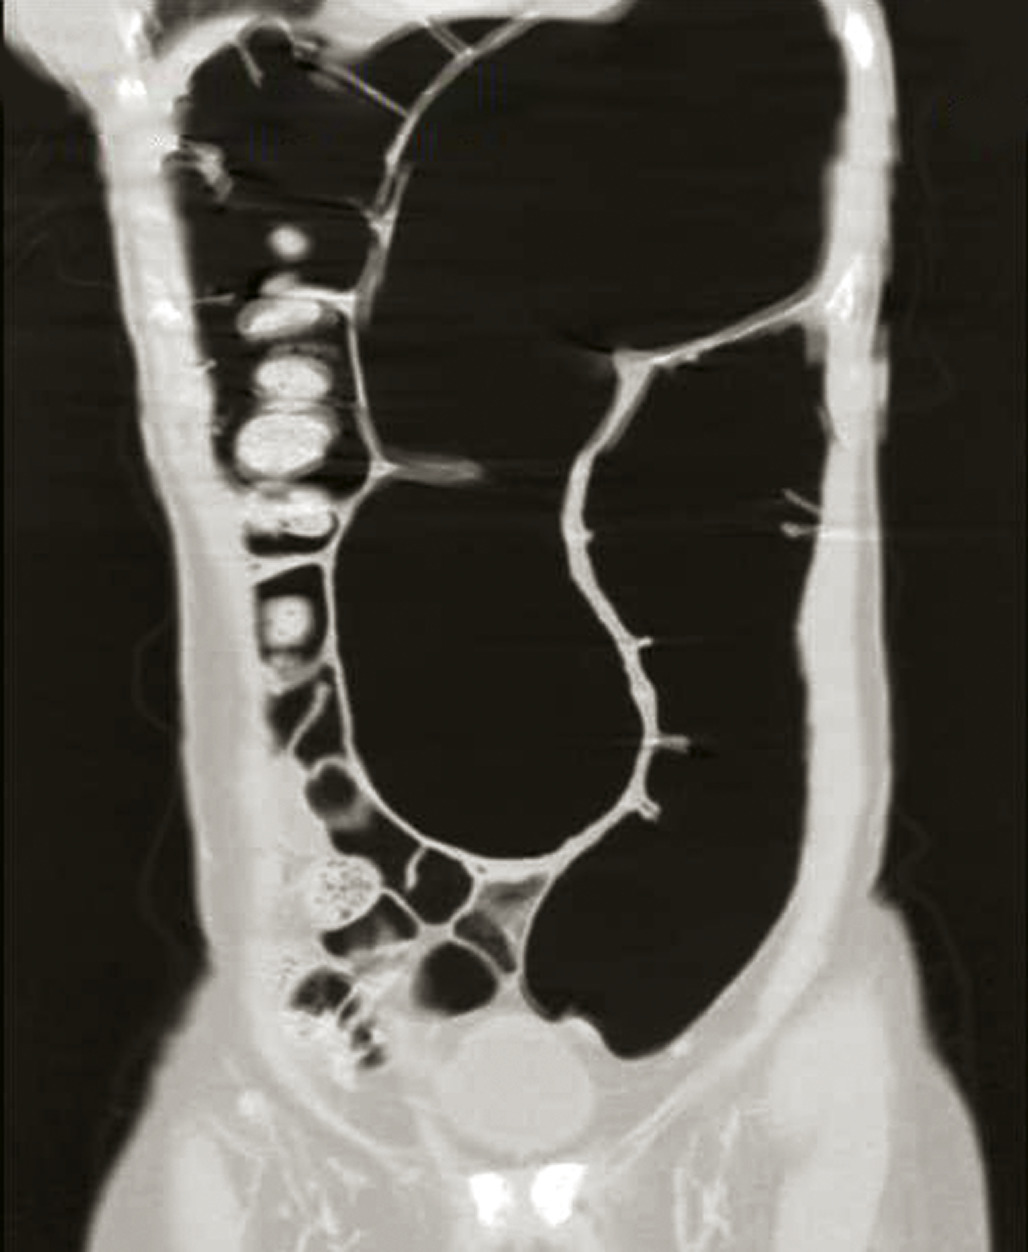

Volvulus du côlon

Ils sont une cause rare d’occlusion intestinale. Tous les segments mobiles du côlon peuvent se volvuler, au premier rang desquels l’anse sigmoïdienne (fig. 6), viennent ensuite les volvulus du côlon droit (fig. 7 et 8) et rarement du côlon transverse.